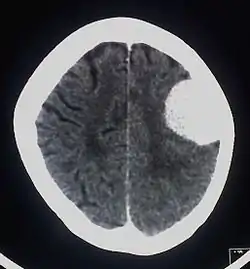

![]() صورة أشعة مقطعية متباينة للدماغ توضح شكل الورم السحائي صورة أشعة مقطعية متباينة للدماغ توضح شكل الورم السحائي | |